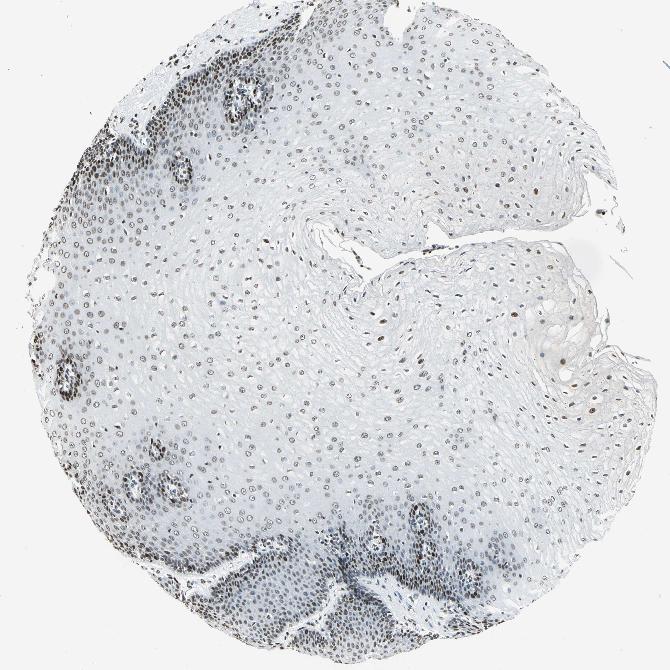

ESOPHAGUS - Antibody stainingi

Antibody staining in the annotated cell types in the current human tissue is reported as not detected, low, medium, or high, based on conventional immunohistochemistry profiling in selected tissues. This score is based on the combination of the staining intensity and fraction of stained cells.

Each image is clickable and will lead to virtual microscopy that enables deeper exploration of all samples and also displays staining intensity scores, fraction scores and subcellular localization as well as patient and tissue information for each sample.

Antibody HPA004873Antibody CAB004497

Squamous epithelial cells MediumHigh